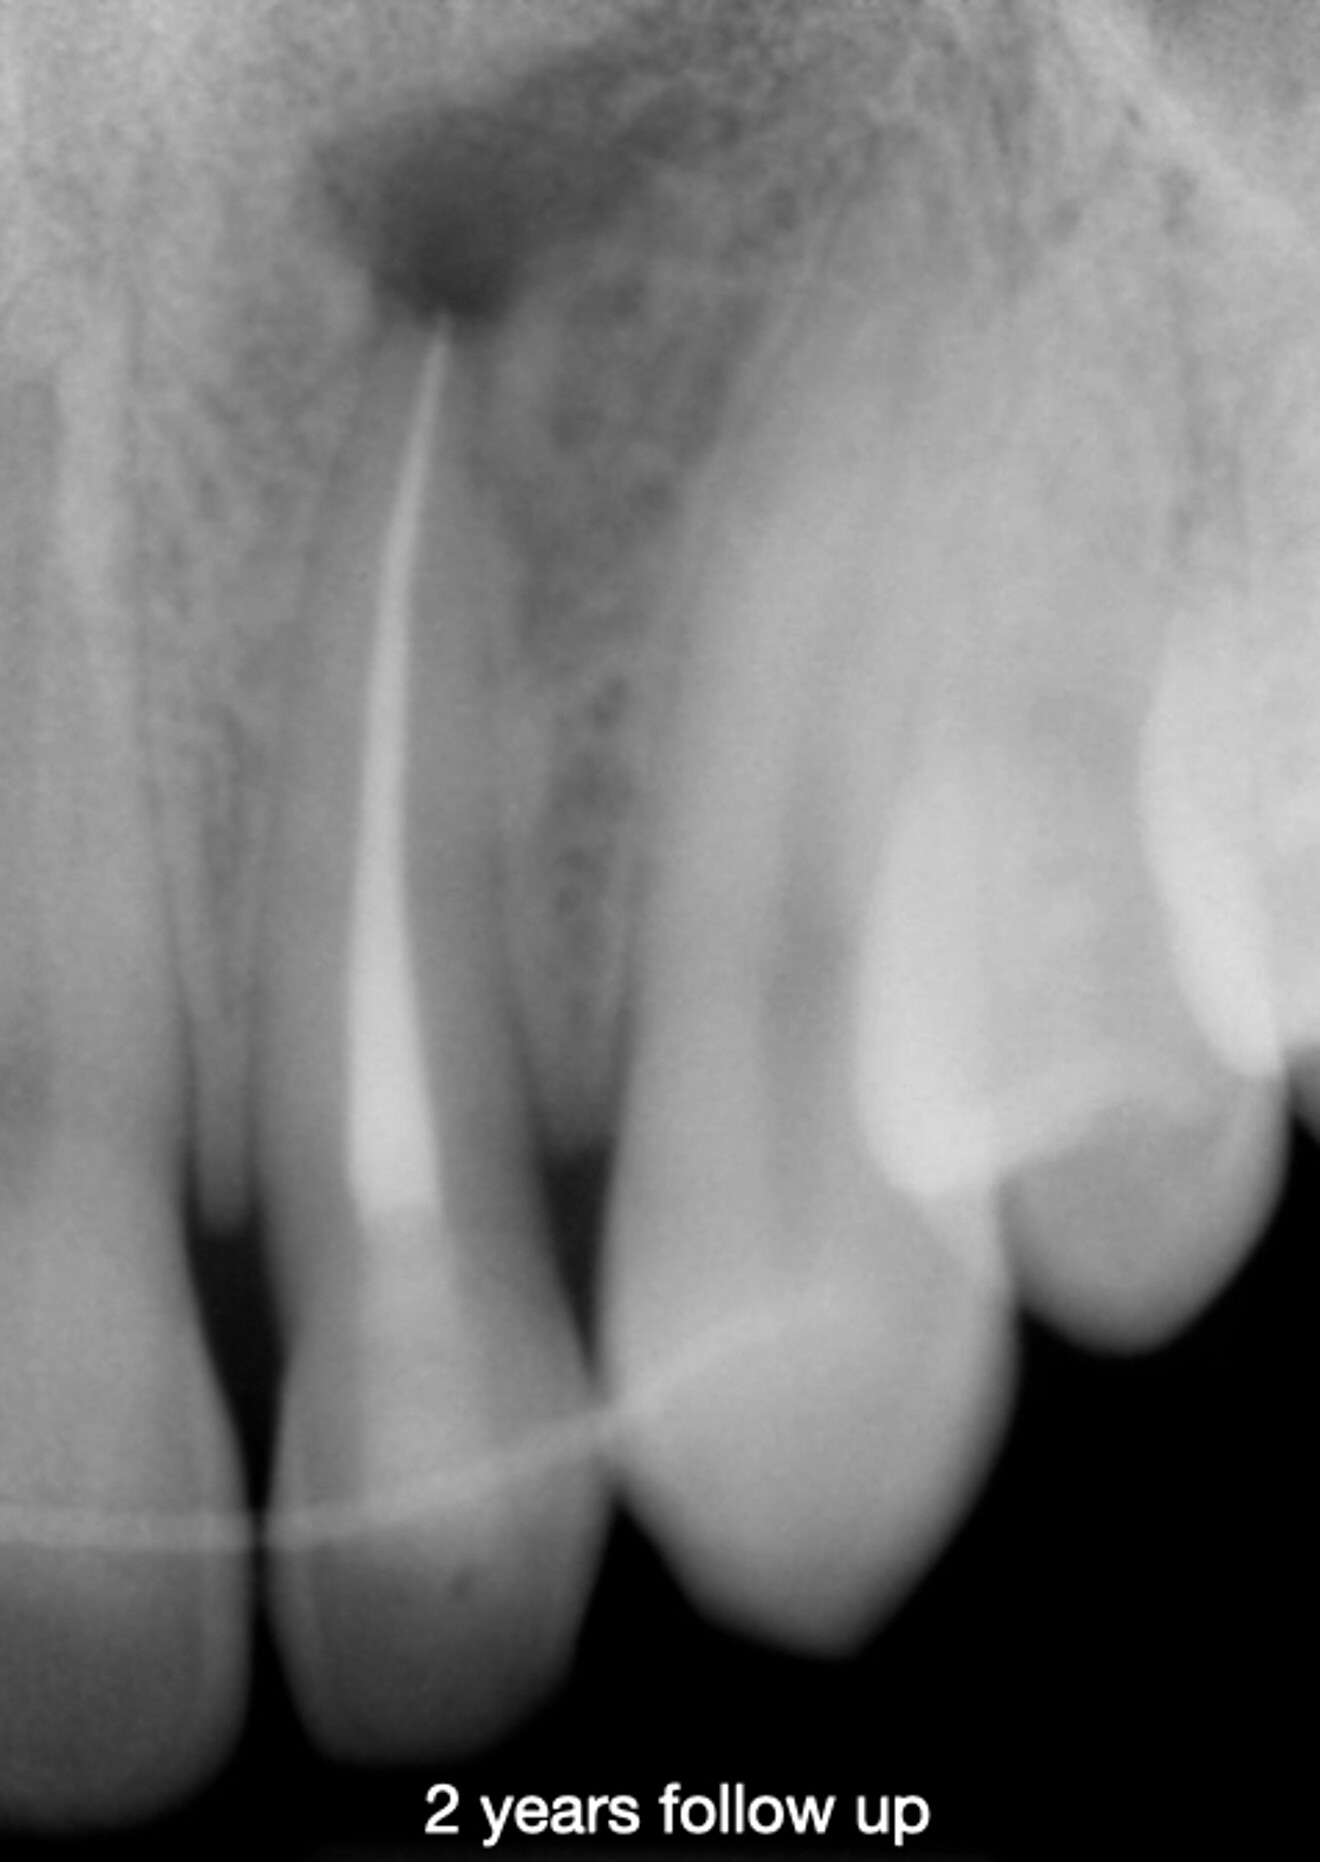

At the two-year follow-up appointment, the radiograph showed healing, but there appeared to be a superimposed image at the apex (Fig. 5). A high-definition CBCT scan taken with the DEXIS OP 3D showed that this was not a lesion but fibrous tissue consistent with physiological healing from the palatal area where the cortical plate had been largely damaged (Fig. 6). Since this was not pathological but a normal reparative process, there was no need to interfere.

Fig. 5c: Radiograph at two years, showing an area of less bone condensation at the root.